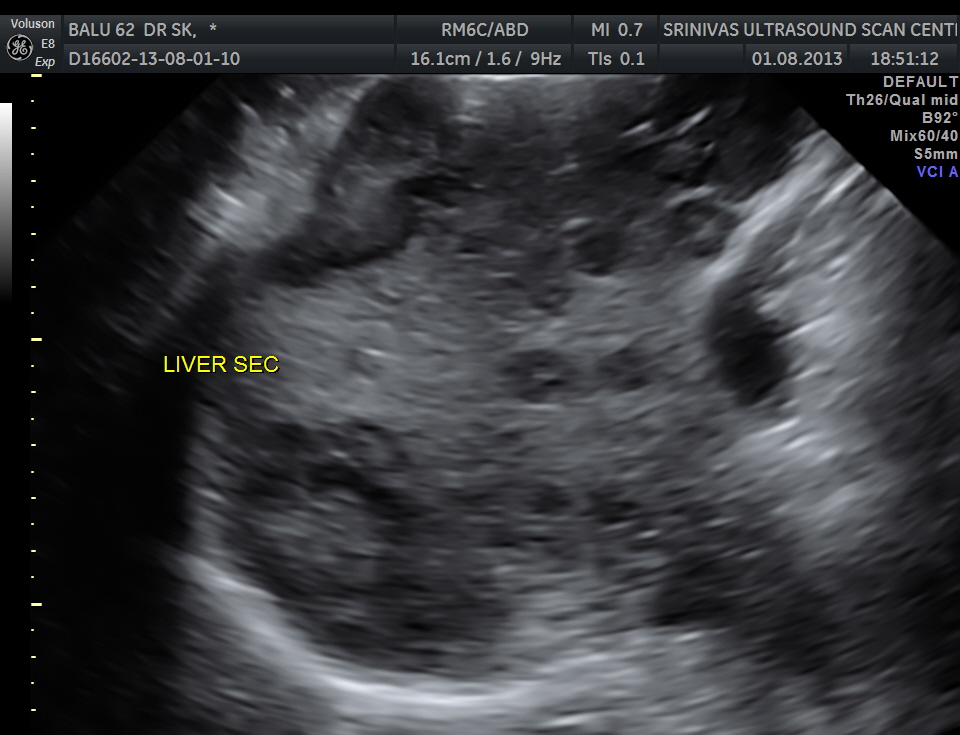

His liver showed multiple secondaries .

secondaries show target appearance or bird’s eye view of mexican hat appearance

DISCUSSION : Generally the target sign or the bird’s eye view of the Mexican hat sign could signify colo-rectal carcinoma.